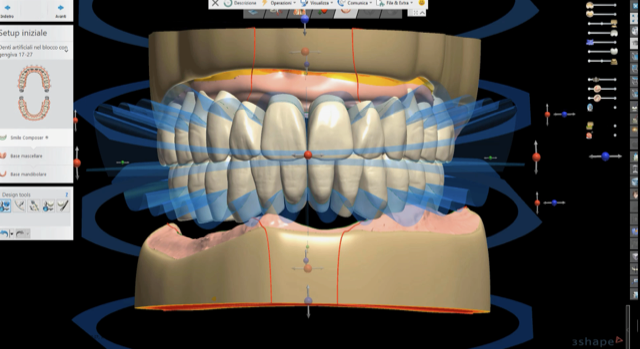

L’assiografia digitale associata a DICOM 3D offre una valutazione reale delle determinanti condilari e una simulazione dei movimenti masticatori. Un software di ricostruzione 3D in pochi minuti consente la ricostruzione completa delle arcate con protesi totali con una valutazione accurata del ripristino della dimensione verticale. La ricostruzione del profilo estetico funzionale integrato (via via condiviso nelle simulazioni in prima visita col paziente) diventa reale.

Fig. 5_La rimozione virtuale della Toronto superiore con software exocad.

Fig. 6_La protesi superiore e inferiore disegnate con le librerie Ivoclar Ivotion.

La protesi totale digitale è un metodo assolutamente predittivo dei tempi di esecuzione. I software di ultima generazione consentono valutazioni assolutamente accurate della congruità delle determinanti occlusali, dei piani di svincolo, della simulazione di movimenti masticatori. Il paziente riceve una soluzione immediata in giornata, dalla bonifica completa alla riabilitazione totale mobile anche di entrambe le arcate.

La soluzione in una singola seduta della protesi totale mobile diventa grazie al metodo della scansione intraorale delle arcate il progetto protesico immediato e il fraseggio con vhf R5 a 5 assi del disco Ivotion Ivoclar Vivadent, proprietario della Shell Geometry. Nella nostra esperienza clinica questo tipo di processo ottimizza tempi e costi nel protocollo di riabilitazione totale in Day Dentistry.